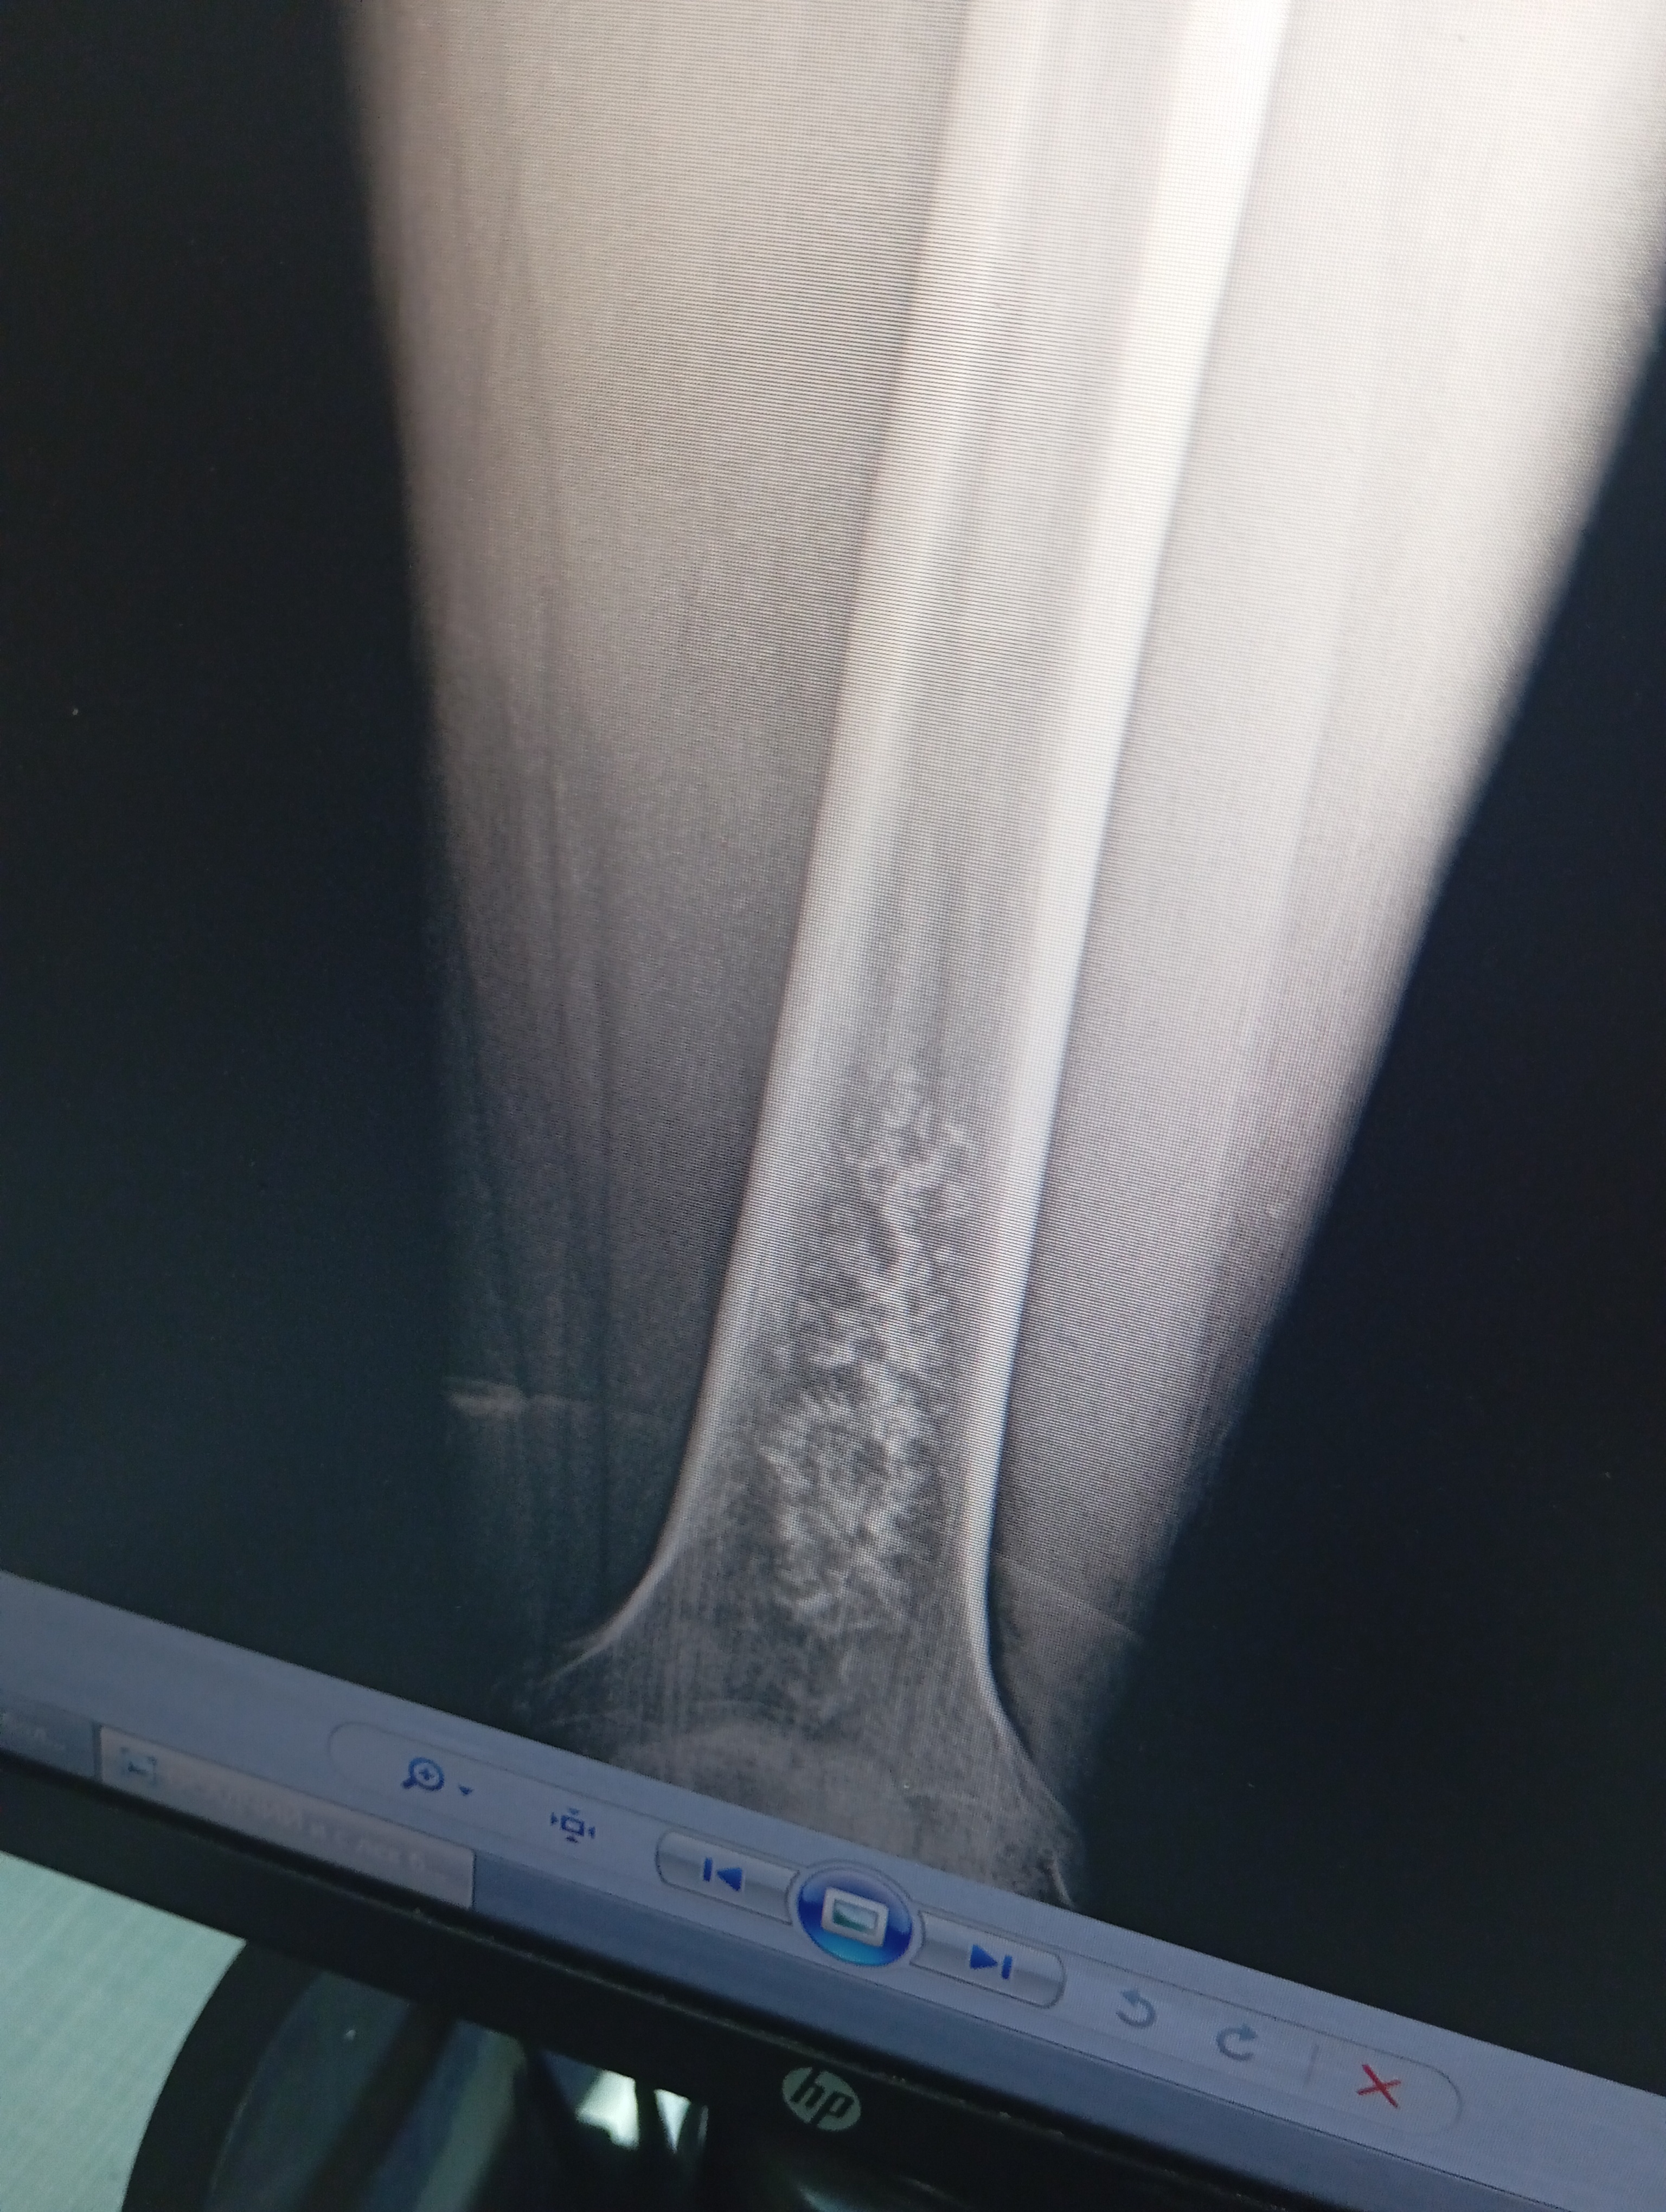

Дорого времени суток, уважаемые врачи! Болело в районе нижней трети левого бедра. В течении года, грешил на сустав коленный. Но боль усиливалась, и стала не выносимой. Сегодня сделали рентген, обнаружили патологию. Что это такое сказать не могут. Посмотрите снимок, пожалуйста. Что это можно быть??? Заранее спасибо!

• Кликните для загрузки файла IMG_20241218_203119.jpeg